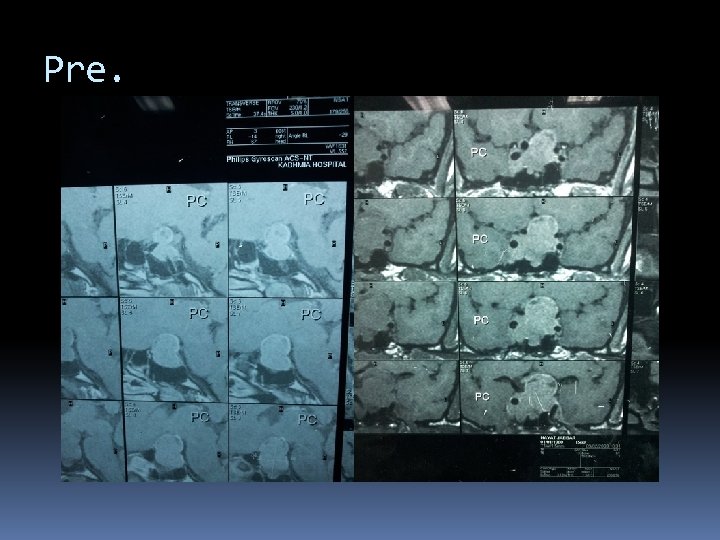

Pre.

Post

Post medical.